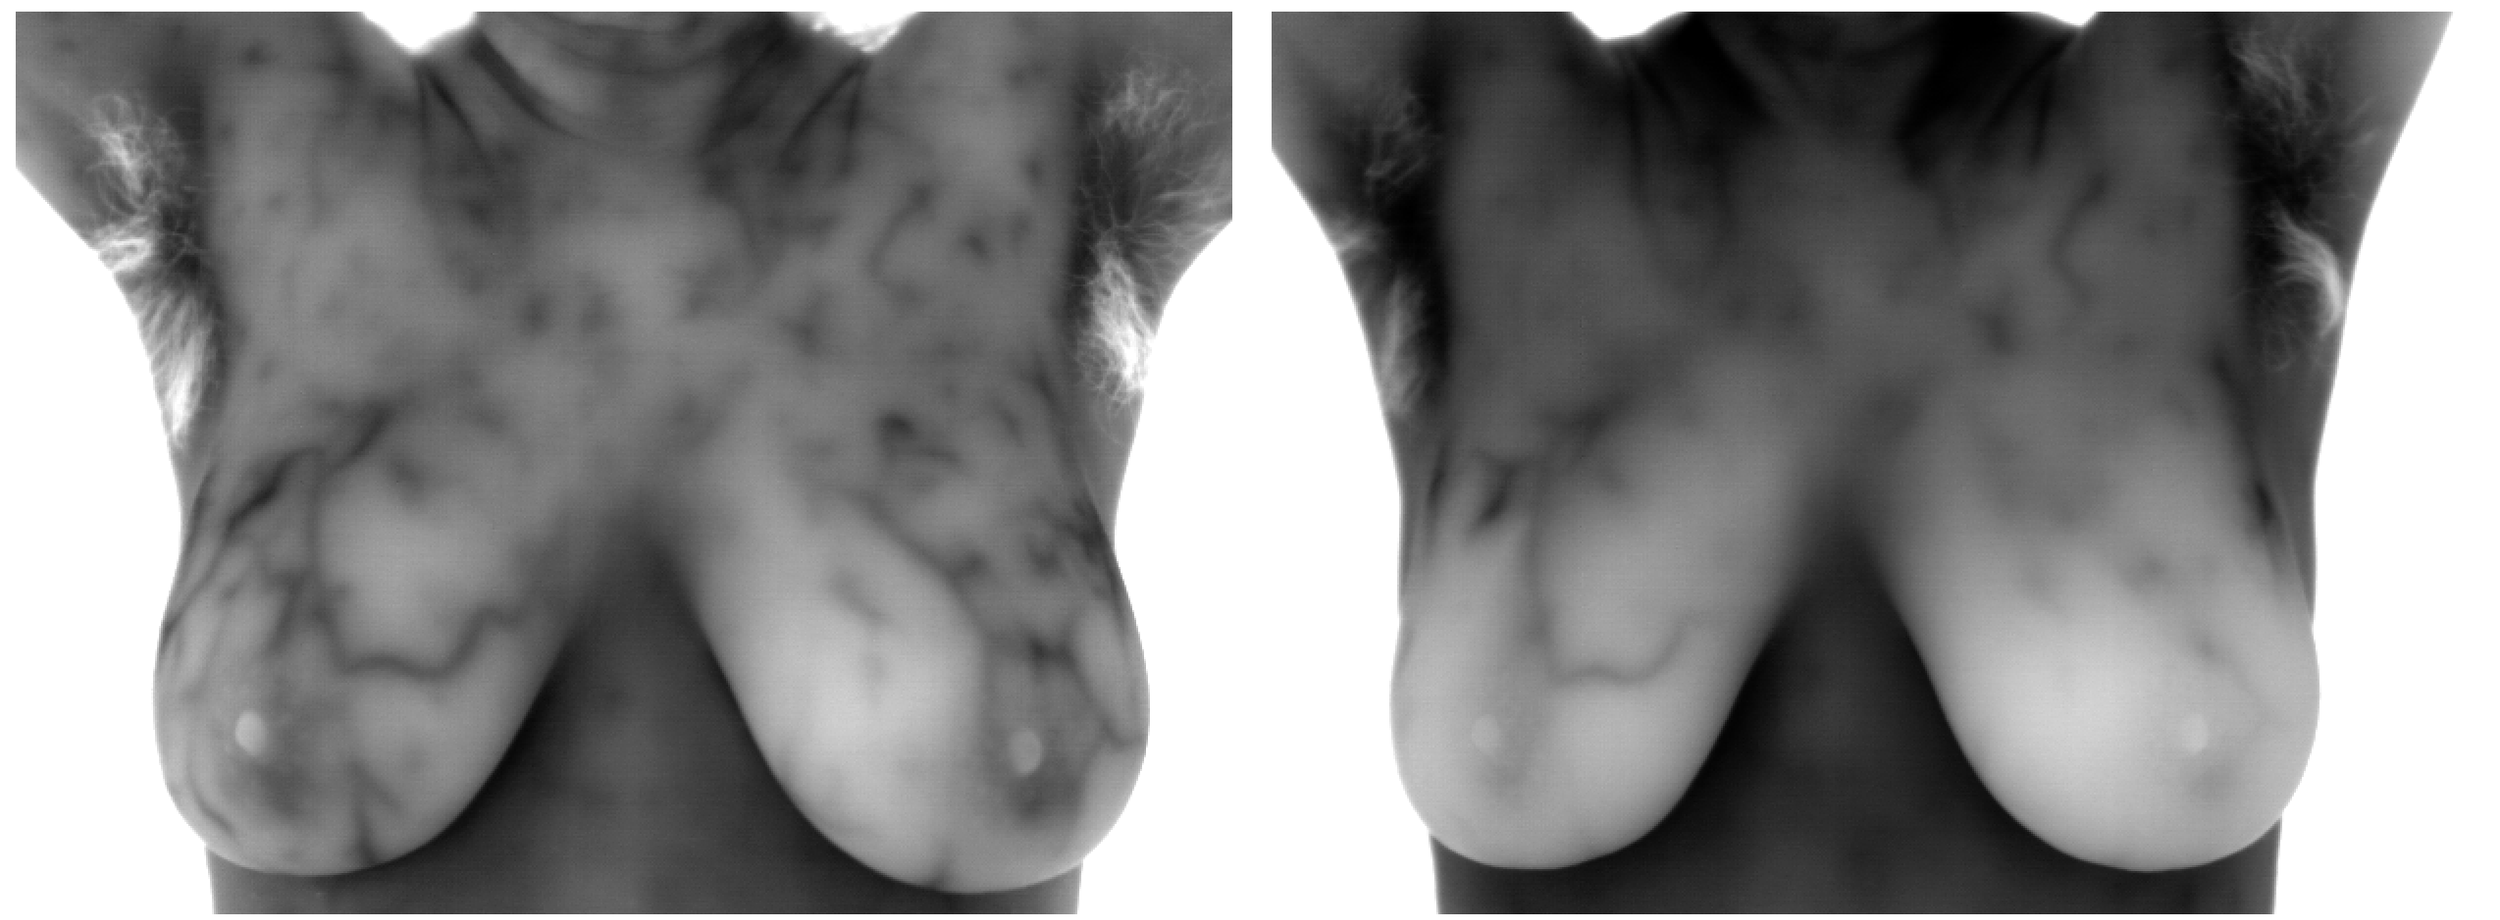

2025's Biggest Turnaround in Pictures! The Power of Compounded Progesterone Pill on Estrogen Dominance Illustrated

Black & White images show the”significant” improvement in the pattern of estrogen dominance in approximately 5 months.

This client’s story is fascinating and illustrates how important it can be to get the highest possible quality of any medication, particularly a hormone. Her first attempt at using progesterone to improve estrogen dominance symptoms was via Prometrium, a commercially available bio-identical brand. Unfortunately, 100 mg made her feel like a zombie so her doctor switched her to a compounded (personally mixed for her) progesterone pill. No more zombie effect and she was able to increase to 200 mg. Images above show the powerfully positive risk-lowering effects in under six months.

Images depict her second and third visits. Her second visit showed worsening since the first visit so she and her doctor, Kathryn Walker at Renu, developed a plan and executed it beautifully to reverse the trend!